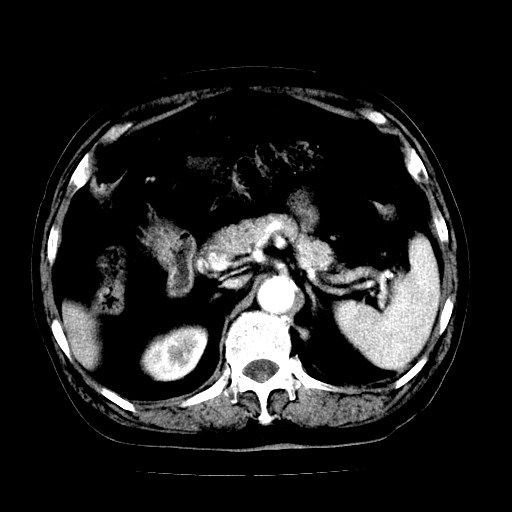

男,71岁,皮肤黄染四天。

肝内外胆管及胆总管上段扩张,考虑为梗阻所致,建议mrcp检查。

考虑胆总管癌并肝内外胆管扩张。

胆管癌并肝内外胆管扩张。

支持考虑胆总管癌并肝内外胆管扩张。 局部应薄扫。心包钙化。

胰腺上端胆总管内见软组织影,强化不明显,结合临床,还是考虑低位梗阻性黄疸,胆总管癌可能性大